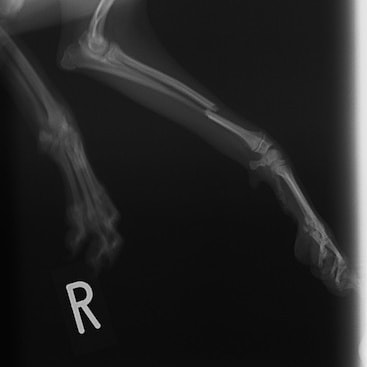

症例3:キルシュナーワイヤーのピンニングによる整復

ペルシャ猫 11ヶ月齢 雄

他院にて左大腿骨遠位の成長板骨折(salter-harrisⅠ型)が認められており、治療相談を目的として来院。当院にて、キルシュナーワイヤーを用いたピンニングにより骨折部位の整復を行いました。術後の経過は良好で、現在も経過観察中です。

術前レントゲン